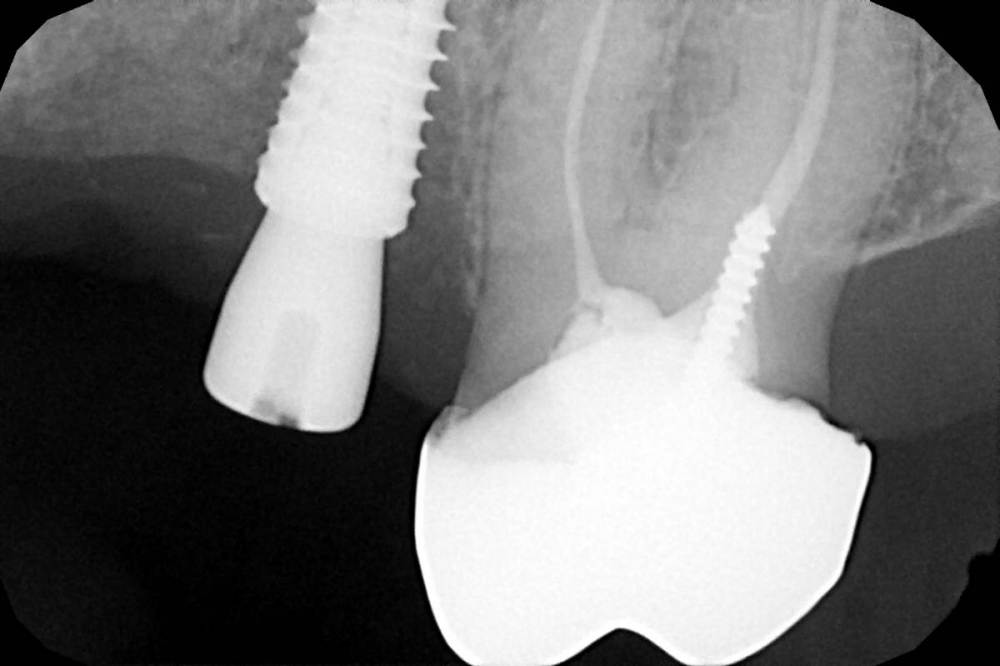

Женька Опубликовано 19 апреля, 2021 Автор Поделиться Опубликовано 19 апреля, 2021 Rg Ссылка на комментарий

Женька Опубликовано 21 июля, 2021 Автор Поделиться Опубликовано 21 июля, 2021 3 месяца минуло... клык на торке 30 неприятные ощущения второй премоляр на 10 и подвижность... отправил на кт. Всё насмарку... Ссылка на комментарий

Женька Опубликовано 22 июля, 2021 Автор Поделиться Опубликовано 22 июля, 2021 @Карен Аванесов скажем так. Один из этих имплантатов я уже переустанавливал по гарантии (то есть с другой стороны год назад ставил 2, выжил 1, этот 1 и пошел на замену по гарантии, но на другую сторону). Так что теперь планирую достать и просто напросто всё зашить и ждать (вопрос к коллегам, сколько вы ждёте обычно?). Затем по двухэтапному протоколу, без всяких формиков одномоментных поставить и зашить под заглушки... Иначе видимо это работать не будет. Касаемо финансов это ёще одна бесплатная переделка (ну расходники не в счёт) Ссылка на комментарий

kramer Опубликовано 22 июля, 2021 Поделиться Опубликовано 22 июля, 2021 Вот до чего доводят соцсети. Какой смысл было делать одномоментно, зная что а) курение б) алкоголь в) нехилый дефект вестибулярно г) мануальные навыки требуют улучшения. Что стоило удалить и через 1,5 месяца спокойно поставить, максимально снизив риски? Видимо, желание доказать окружающим себе свою МОЩЩЩ Ссылка на комментарий

Женька Опубликовано 22 июля, 2021 Автор Поделиться Опубликовано 22 июля, 2021 @kramer нет, ни в коем случае никому ничего не хотел доказывать. Тешить своё эго это не про меня... Скорее хотел как раз улучшить навыки одномоментной имплантации. Ну и помочь поскорее обрести человеку зубы. Благими намерениями как говорится. Отрицательный опыт тоже опыт... Ссылка на комментарий